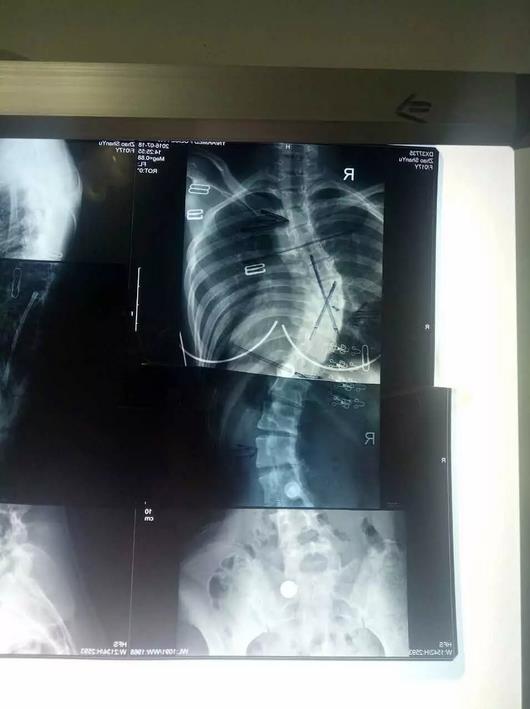

脊髓损伤 T10 A型

青少年脊柱侧弯35度

脊柱侧弯矫形器

矫正后侧弯5度